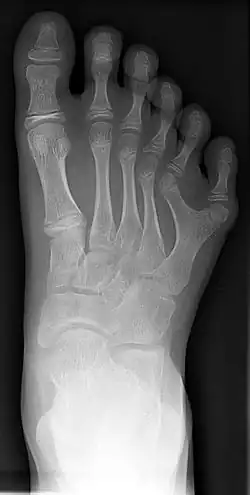

Die Polydaktylie (von griechisch πολύς polýs ‚viel‘ und δάκτυλος dáktylos ‚Finger‘, wörtlich also „Vielfingerigkeit“)[1] bezeichnet eine vererbbare, angeborene, anatomische Besonderheit bezüglich der Anzahl zusätzlicher Hand- und/oder Fußgliedmaßen. Die Besonderheit kann bei Menschen, aber auch bei Katzen,[2] Hunden,[3] Vögeln,[4] Meerschweinchen[5] und anderen Tieren vorkommen. Menschen mit Polydaktylie verfügen über mehr als die übliche Anzahl an Fingern oder Zehen. Besonders häufig findet sich ein- oder beidseitig ein jeweils sechster Finger (meist ein unvollständiger Doppeldaumen) oder doppelter großer Zeh (Hexadaktylie). Polydaktylie wird meist autosomal-dominant vererbt.

Die gebräuchlichste Unterscheidungsform ist präaxiale Polydaktylie (Daumenseite, Abb. 3, 6, 7, 9), postaxiale Polydaktylie (Handaußenseite, Abb. 1, 2, 4) und (selten) zentrale Polydaktylie am Ring-, Mittel- oder eher noch am Zeigefinger. Zentrale Polydaktylie ist oft mit Syndaktylie verbunden. Die Kombination wird zur Polysyndaktylie. Andere Fehlbildungen an Fingern und Zehen sind Dysmelie, Brachydaktylie und Oligodaktylie.